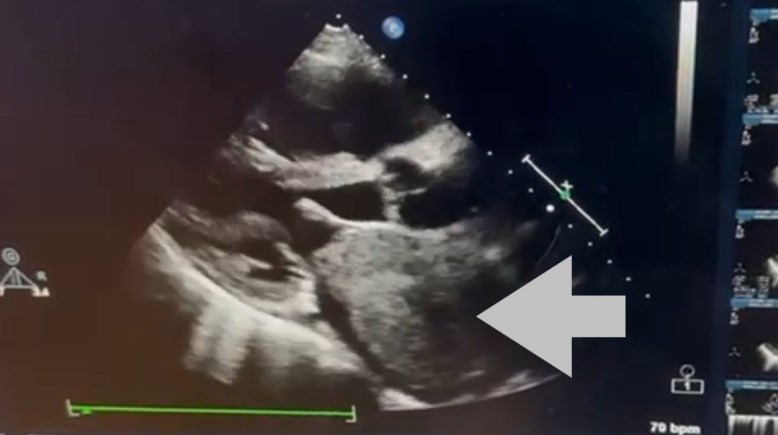

بحجم قبضة اليد.. استئصال ورم ضخم من قلب مريض سبعيني بقصر العيني